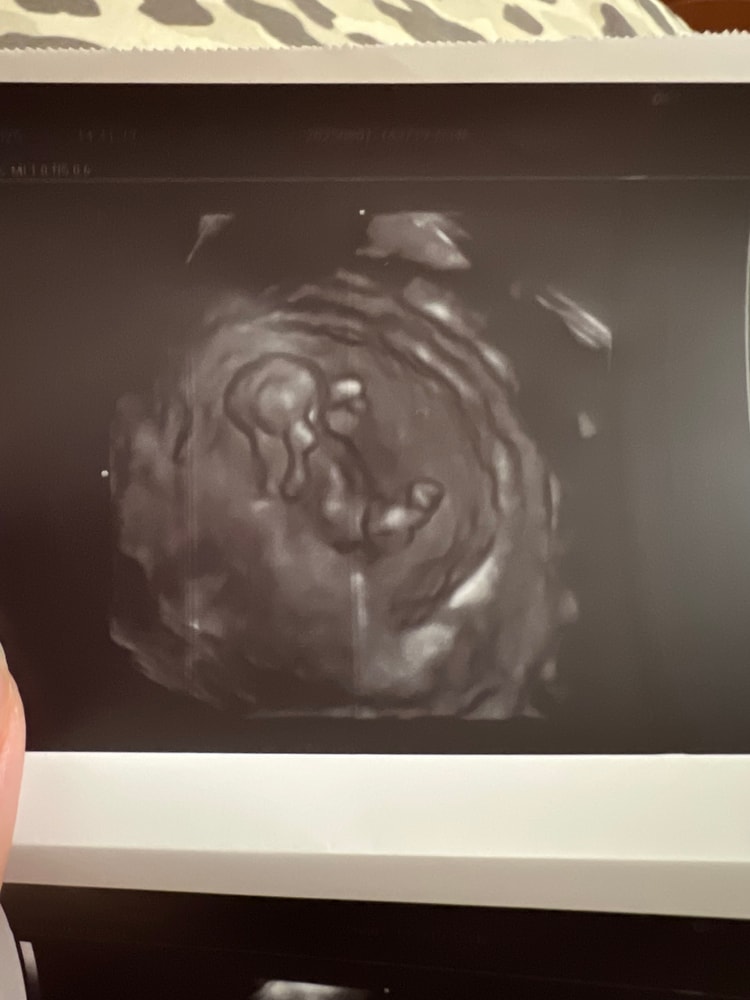

УЗИ 11 недель

УЗИ, КТГ, доплерНеделю болела,пришлось пить антибиотики,после того как вылечилась соотвественно побежала смотреть малышарика.Сегодня поставили срок по узи 11 недель,врач сделала мне 3д снимки черно белые ,я посмотрела на снимок и ничего не поняла кроме рук и ног😇Но главное что сказали что все хорошо.Кто нибудь делал такие снимки на таком раннем сроке?Приложу фото может кому будет интересно)

Какой крохотный 😅 голову тоже видно))

Ryabina, целых 4,5 см человек))На экран тоже выводила,как будто на экране понятнее было)))